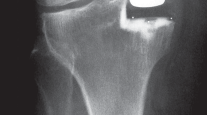

التصوير الطبي ضروري لتأكيد التشخيص وتحديد مدى تلف المفصل:

-

الأشعة السينية العادية (Plain Radiographs):

- المنظر الأمامي الخلفي (AP): يُظهر الركبة من الأمام.

- المنظر الجانبي (Lateral): يُظهر الركبة من الجانب.

- المنظر الخلفي الأمامي المثني (PA Flexed): يسمح بتقييم أفضل للجزء الخلفي من الركبة وقد يكشف عن تغيرات أكبر في الحجرة الخلفية الوحشية.

- منظر شروق الشمس (Sunrise/Patellofemoral): لتقييم المفصل الرضفي الفخذي.

- الأشعة السينية الطويلة للطرف السفلي بالكامل (Full-length standing radiographs): من الورك إلى الكاحل، وهي مفيدة جدًا، خاصة إذا تم استخدام تقنيات الملاحة الحاسوبية. تُظهر هذه الأشعة المحاذاة الكلية للطرف السفلي.

1. التخطيط قبل الجراحة

-

القوالب المسبقة (Preoperative Templating):

يتم استخدام الأشعة السينية لتحديد حجم وموضع المكونات المزروعة بدقة قبل الجراحة.